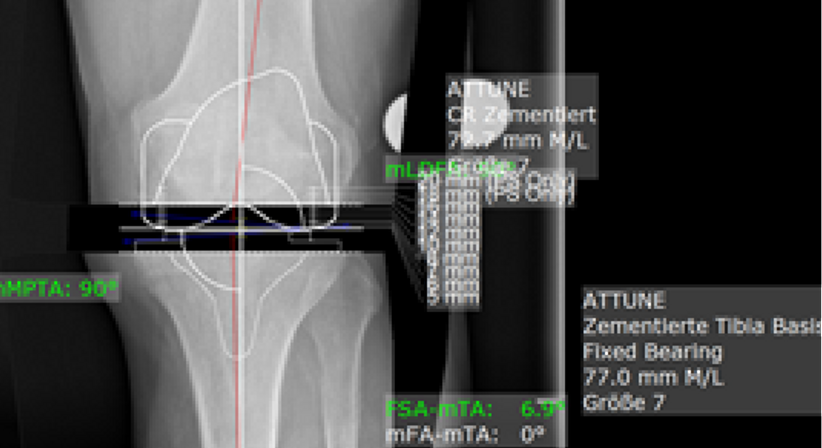

Totalendoprothese (Knie-TEP)

Eine Totalendoprothese des Knies, auch als Knie-TEP abgekürzt, ist ein chirurgischer Eingriff, bei dem das gesamte Kniegelenk durch eine künstliche Prothese ersetzt wird. Die Prothese besteht aus Metall und Kunststoff und ahmt die natürliche Struktur und Funktion des Kniegelenks nach.